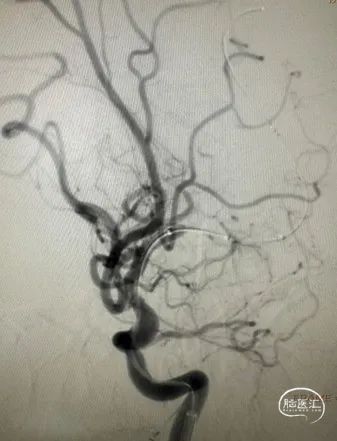

DSA

左侧大脑中动脉重度狭窄,近端:1.78mm,远端:2.18mm,最窄:0.25mm,长度:14.70mm,狭窄率约:89%。

扩张后即刻造影。

支架释放后造影。

患者麻醉复苏后无神经功能障碍。患者术后标准正侧位造影。